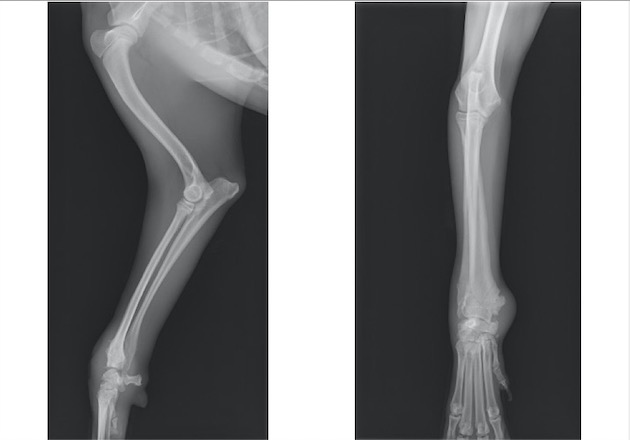

ソファーの背もたれから落下後、右前肢居城を主訴に来院。

視診上、両前肢の明らかな左右差は認められませんでしたが、触診検査において肘関節における圧痛を確認しました。

単純X線検査を実施したところ、上腕骨遠位外顆骨折が認められ、上腕骨遠位の成長板をまたぐ骨折であったことから成長板骨折(Salter-Haris Type4)と診断して外科的処置を実施しました。

背掌像より上腕骨遠位外顆の骨折が認められました。